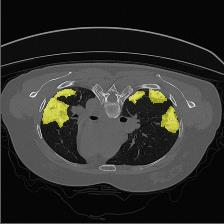

Medical image segmentation is one of the most fundamental tasks concerning medical information analysis. Various solutions have been proposed so far, including many deep learning-based techniques, such as U-Net, FC-DenseNet, etc. However, high-precision medical image segmentation remains a highly challenging task due to the existence of inherent magnification and distortion in medical images as well as the presence of lesions with similar density to normal tissues. In this paper, we propose TFCNs (Transformers for Fully Convolutional denseNets) to tackle the problem by introducing ResLinear-Transformer (RL-Transformer) and Convolutional Linear Attention Block (CLAB) to FC-DenseNet. TFCNs is not only able to utilize more latent information from the CT images for feature extraction, but also can capture and disseminate semantic features and filter non-semantic features more effectively through the CLAB module. Our experimental results show that TFCNs can achieve state-of-the-art performance with dice scores of 83.72\% on the Synapse dataset. In addition, we evaluate the robustness of TFCNs for lesion area effects on the COVID-19 public datasets. The Python code will be made publicly available on https://github.com/HUANGLIZI/TFCNs.